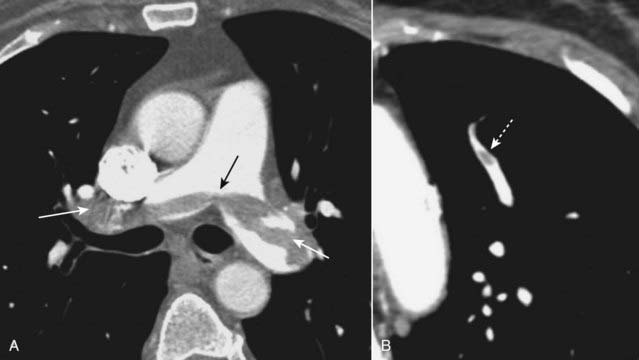

image On CT-PA, acute pulmonary emboli appear as partial- or complete-filling defects centrally located within the contrast-enhanced lumina of the pulmonary arteries (Fig. 12-21).

image

Figure 12-20 Hampton hump.

There is a wedge-shaped, peripheral air-space density present (dotted white arrow) associated with filling defects in both the left and right pulmonary arteries (solid white arrows). The wedge-shaped infarct is called a Hampton hump. Without the associated emboli present, the pleural-based airspace disease could have a differential diagnosis that includes pneumonia, lung contusion, or aspiration.

Figure 12-21 Saddle and peripheral pulmonary emboli.

Acute pulmonary emboli appear as partial or complete filling defects centrally located within the contrast-enhanced lumina of the pulmonary arteries. A, A large pulmonary embolus almost completely fills both the left and right pulmonary arteries (solid white and black arrows). This is a saddle embolus. B, A small, central filling defect is seen in a more peripheral pulmonary artery (dotted white arrow). This pulmonary artery seems to be floating disconnected in the lung because the plane of this particular image does not display its connection to the left pulmonary artery.